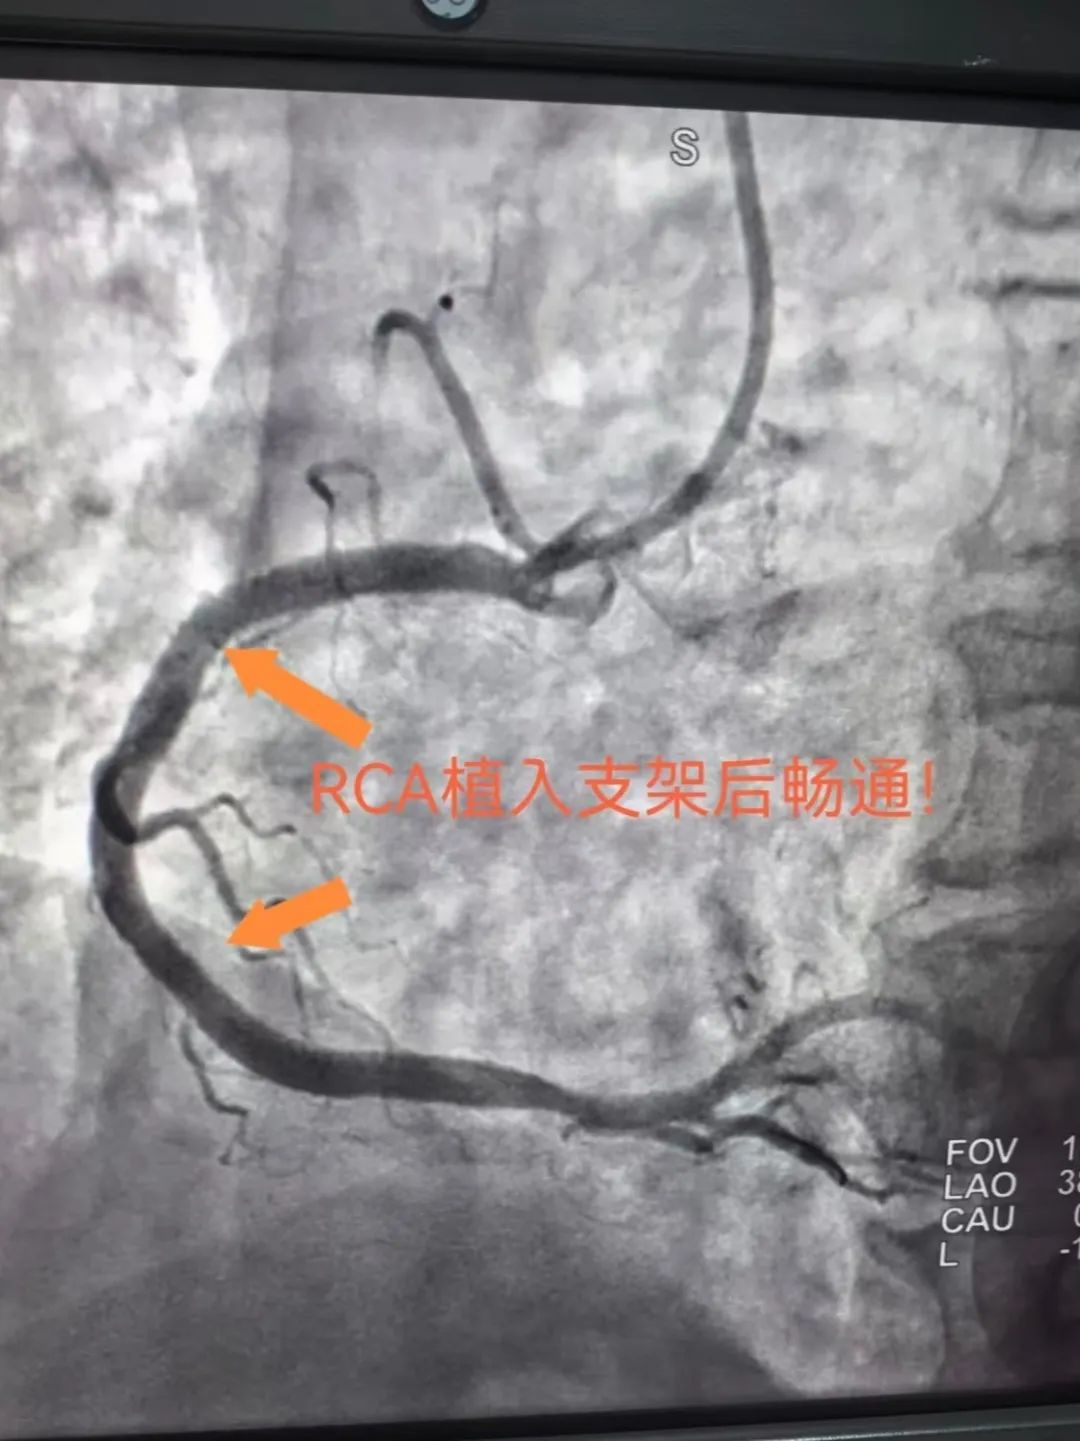

在转运途中,训练有素的急救团队已开始争分夺秒的术前准备:转运途中给予「心梗一包药」、注射肝素抗凝、建立静脉通路、抽取血标本······所有操作精准到位,为后续治疗赢得先机。7 时 56 分,救护车抵达医院,直接驶向早已准备就绪的导管室。胸痛团队医护配合默契,手术流程行云流水,8 时 22 分,导丝通过闭塞的血管,之后成功开通——从入院到导丝通过时间(DTW 时间),仅用 26 分钟!